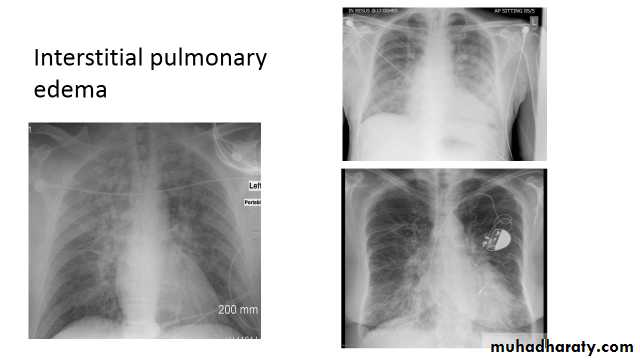

pulmonary interstitial oedema

Pulmonary edema is a broad descriptive term and is usually defined as an abnormal accumulation of fluid in the extra-vascular compartments of the lung .

Septal lines, also known as Kerley lines, are seen when the interlobular septa in the pulmonary interstitium become prominent. This may be because of lymphatic engorgement or edema of the connective tissues of the interlobular septa. They usually occur when pulmonary capillary wedge pressures reach 20-25 mmHg ,

Classification

Kerley A lines

These are 2-6 cm long oblique lines that are <1 mm thick and course towards the hila. They represent thickening of the interlobular septa

Kerley B lines

These are 1-2 cm thin lines in the peripheries of the lung. They are perpendicular to and extend out to the pleural surface . They represent thickened sub pleural interlobular septa and are usually seen at the lung bases.